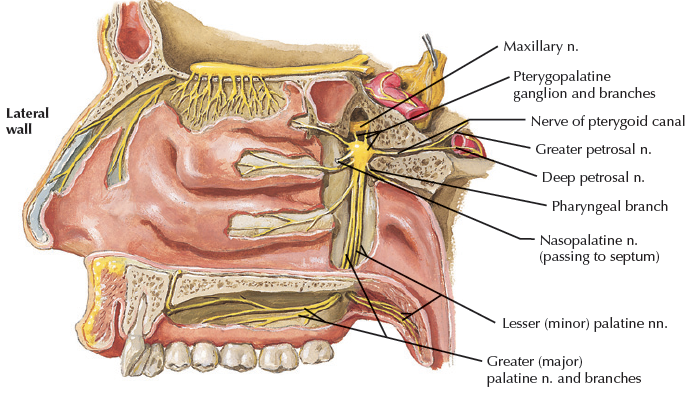

Pterygopalatine ganglion

Pterygopalatine ganglion

- Greater/lesser palatine n.

- Nasopalatine n.

- Post. sup. nasal n.

- Pharyngeal n.

Pterygopalatine Fossa

Sphenopalatine foramen

Nasal cavity

- Nasopalatine n.

- Post. sup. nasal n.

- Sphenopalatine vessels

Palatine canal

Hard & soft palate (Oral cavity)

- Greater palatine n. and vessels

- Lesser palatine n. and vessels